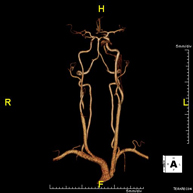

Prova diagnòstica no invasiva que consisteix en l'obtenció d'imatges d'alta definició anatòmica de les artèries caròtides i vertebrals a nivell de coll mitjançant l'ús d'un camp electromagnètic i ones de ràdio (amb un emissor i un receptor). No utilitza radiació ionitzant. En la majoria dels casos és necessari l'ús de contrast paramagnètic (Gadolini). Permet un estudi angiogràfic no invasiu gràcies a la injecció de Gadolini amb posterior reconstrucció en 2D i 3D, gràcies a estacions de treball especialitzades. Indicacions: problemes circulatoris cerebrals i síncope. - Angio-RM d'Aorta Toràcica

Prova diagnòstica no invasiva que consisteix en l'estudi de l'artèria aorta abdominal per obtenir imatges d'alta definició anatòmica mitjançant l'ús d'un camp electromagnètic i ones de ràdio (amb un emissor i un receptor). És indispensable l'ús de contrast intravenós paramagnètic (Gadolini). No obstant, no utilitza radiació ionitzant. La qualitat de les imatges permet realitzar reconstruccions en 2D i 3D. Està especialment indicada en pacients amb sospita de malaltia vascular de les dues extremitats, en pacients amb malaltia vascular de les dues extremitats com a mapa vascular abans del tractament (percutani o quirúrgic), com a mapa vascular prequirúrgic en pacients amb lesions òssies o musculars que requereixin cirurgia, etc. - Angio-RM Lesión partes blandas